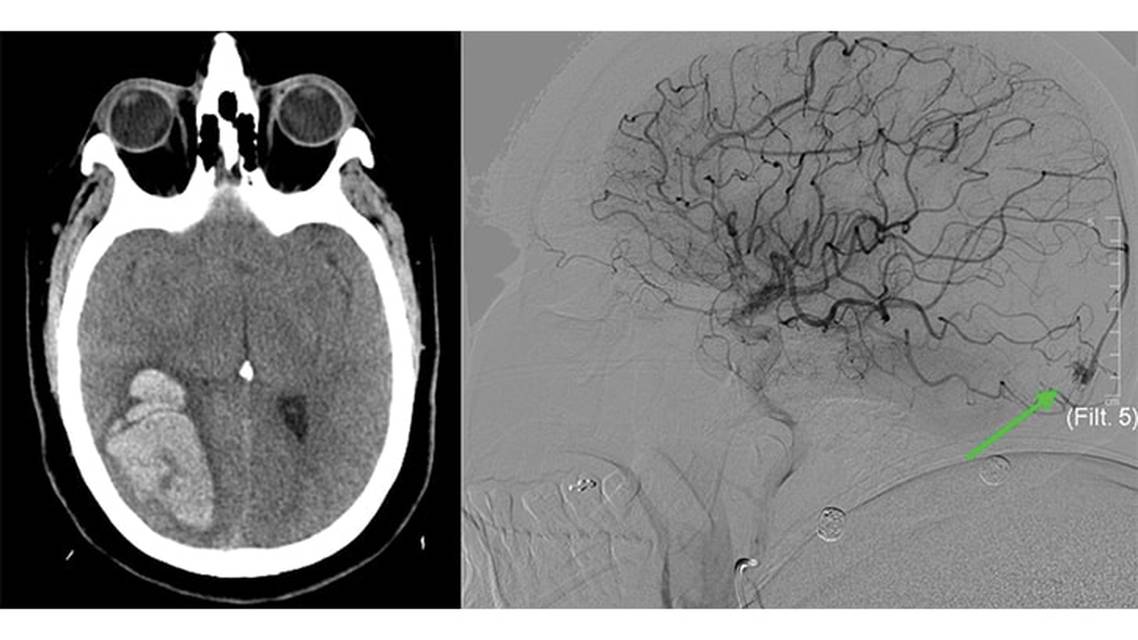

Head CT without contrast (Figure 1A) revealed a right parieto-occipital parenchymal hemorrhage measuring 5.7 x 3.7 x 5 cm with surrounding edema and a midline shift of 5 mm from right to left. PR was then transferred to an outside hospital. Initial CT angiogram of the head and neck was negative for intracranial thrombosis, aneurysm, or other vascular malformations. A CT venogram was performed, which was negative for cerebral venous sinus thrombosis. A nicardipine drip and hypertonic saline were administered and PR was admitted to the intensive care unit for close monitoring and further workup of the intraparenchymal hemorrhage.

Because initial neuroimaging was negative for an underlying etiology for the hematoma, PR underwent digital subtraction angiography (DSA), which revealed a 7 x 6 mm pial arteriovenous fistula (AVF) (Figure 1B) supplied by the right posterior cerebral artery (lateral occipital branch) and the right middle cerebral artery (posterior temporal branches). The nidus was located on the lateral occipital cortical surface. There was a single draining occipital cortical vein to the superior sagittal sinus. There was no feeding artery or nidal aneurysm. Because of the lesion’s distal location and the small caliber of the feeding branches, PR was not a candidate for embolization by interventional radiology.